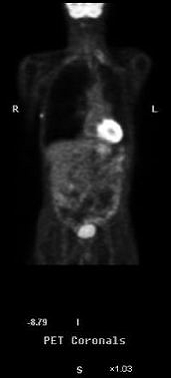

Fig. 3. Structura 18F-FDG, in comparatie cu Fig. 4. Imagine PET cu F FDG:

D-glucoza si 2-deoxi-D-glucoza neoplasm pulmonar primar (lob superior stang) cu

metastaze (paratraheal si in lobul hepatic stang)